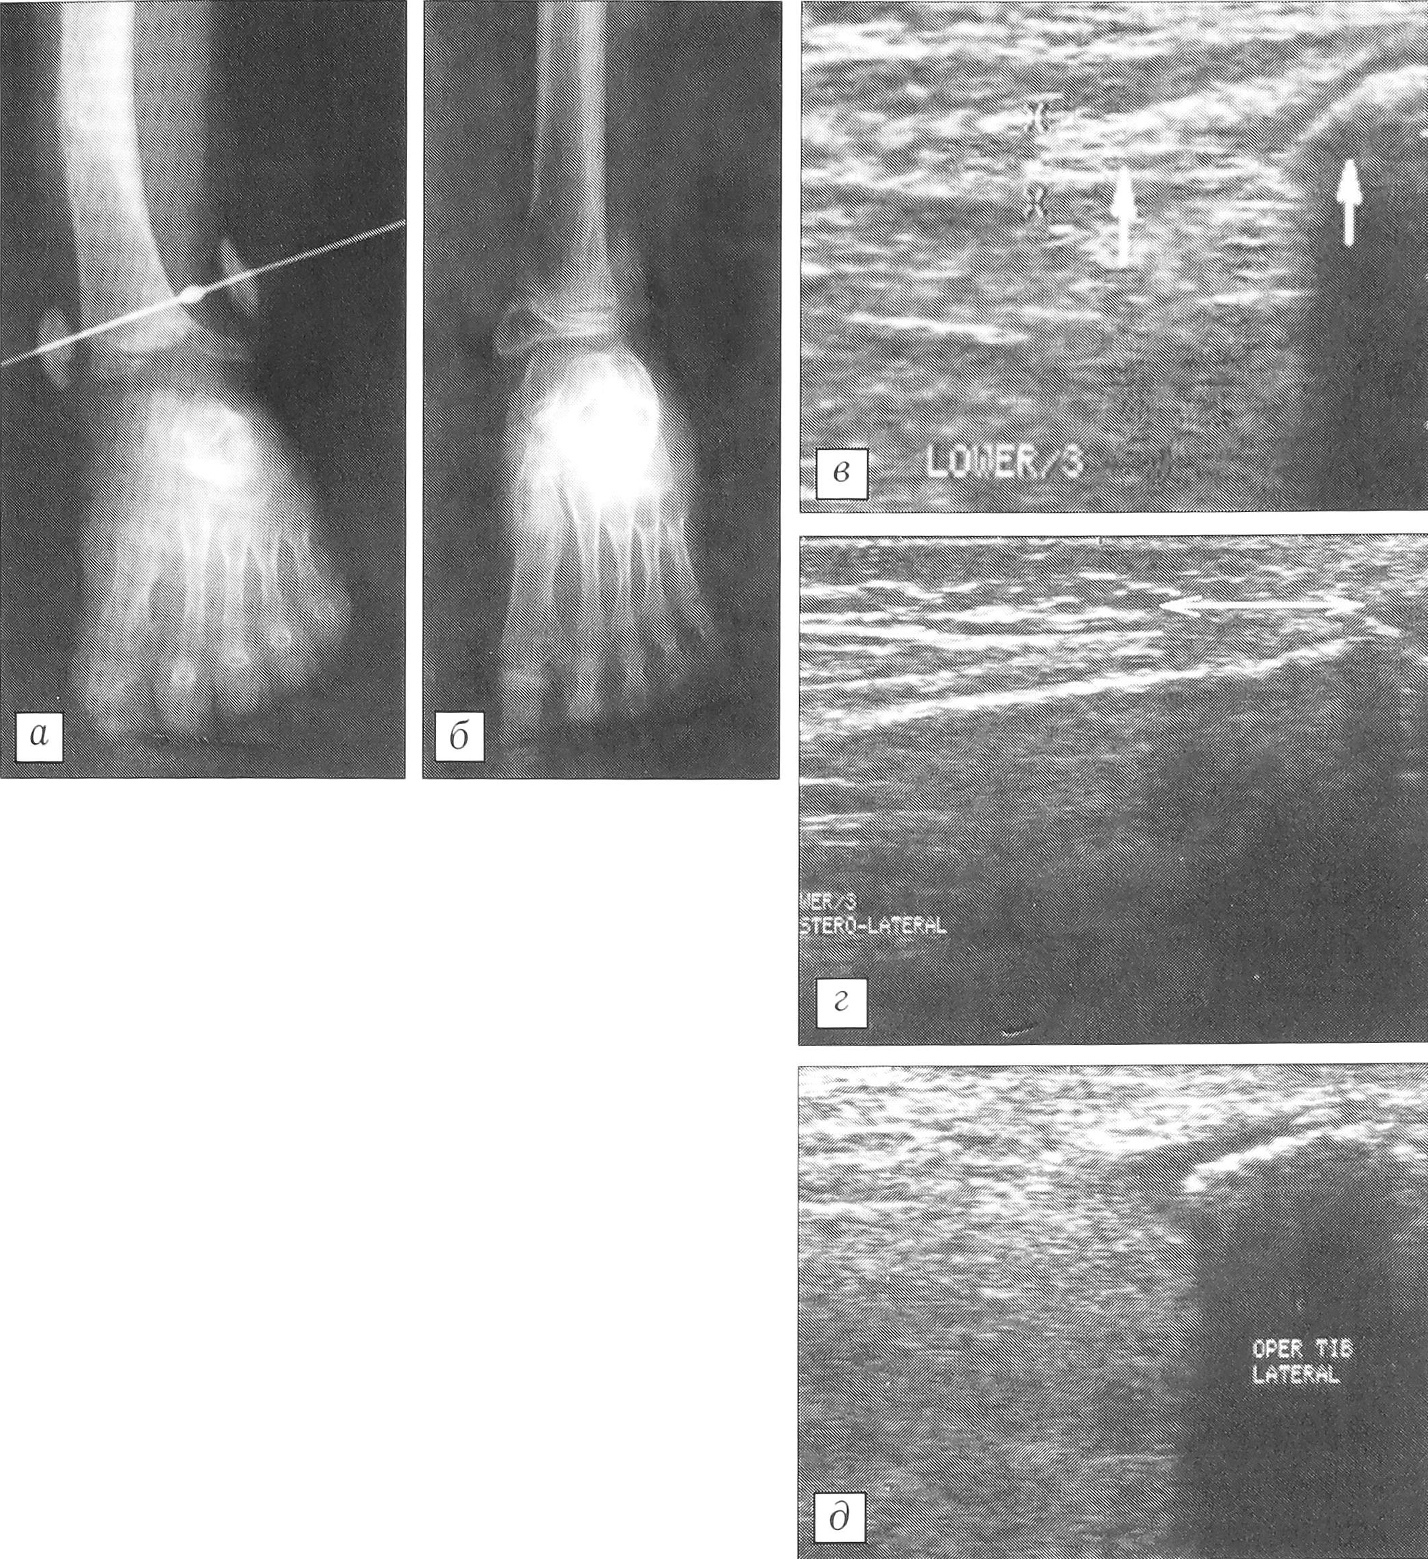

Данные измерений нижнелатерального угла большеберцовой кости и ее деформаций представлены в табл. 3. Из нее видно, что во всех группах после окончания оперативного лечения происходило уменьшение нижнелатерального угла большеберцовой кости по мере увеличения нагрузки на оперированную конечность. Однако в ходе последующего роста конечности наблюдалась тенденция к нормализации этого показателя во 2-й и 3-й группах, более выраженная после резекции фиброзного тяжа. На рис. 4 показана динамика формирования голеностопного сустава у пациента после билокального дистракционного остеосинтеза голени аппаратом Илизарова в сочетании с резекцией малоберцового тяжа. Особо нужно отметить, что нижнелатеральный угол большеберцовой кости в течение 2 лет после оперативного удлинения сегмента не уменьшился. При ультразвуковом сканировании, выполненном через 2,5 года после удаления малоберцового тяжа, констатировано отсутствие какой-либо фиброзно-хрящевой структуры выше рудимента малоберцовой кости.

Рис. 4. Рентгенограммы голеностопного сустава и ультрасонограммы больного И.a — до операции (в возрасте 5 лет);б — через 2,5 года после окончания оперативного удлинения голени с резекцией малоберцового фиброзно-хрящевого тяжа;в — до операции (стрелками указаны фиброзно-хрящевой тяж и рудимент малоберцовой кости);г — через 1 мес после снятия аппарата (указан диастаз на месте резекции тяжа);д — через 2,5 года после окончания лечения: отсутствие какой-либо эхоплотной продольной структуры выше рудимента малоберцовой кости.